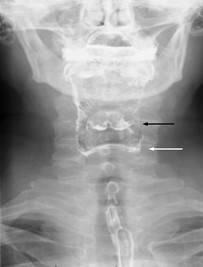

Q50. A patient presents with the injury shown in a lateral X-ray of the nose. What procedure can be done to manage this patient?

- Tilley’s probe

- Luc’s forceps

- Denis Browne probe

- Walsham’s forceps

Answer: D